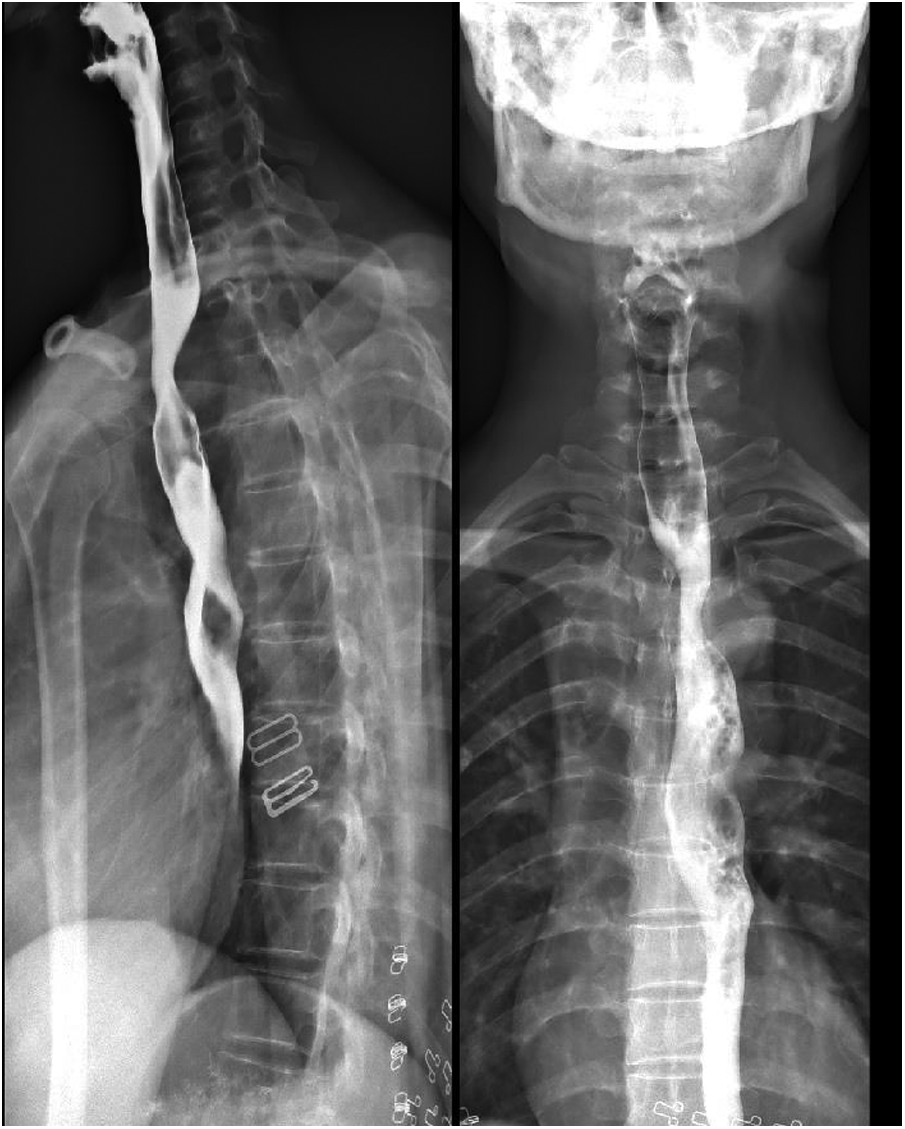

The patient herself complained of no respiratory or swallowing problems. A barium meal examination of the esophagus indicated the presence of vascular indentation in the upper-middle segment, accompanied by local mild-to-moderate narrowing (Figure 3).

Figure 3. Barium meal examination of the esophagus suggested vascular indentation in the upper-middle segment of the esophagus, with mild-moderate narrowing.